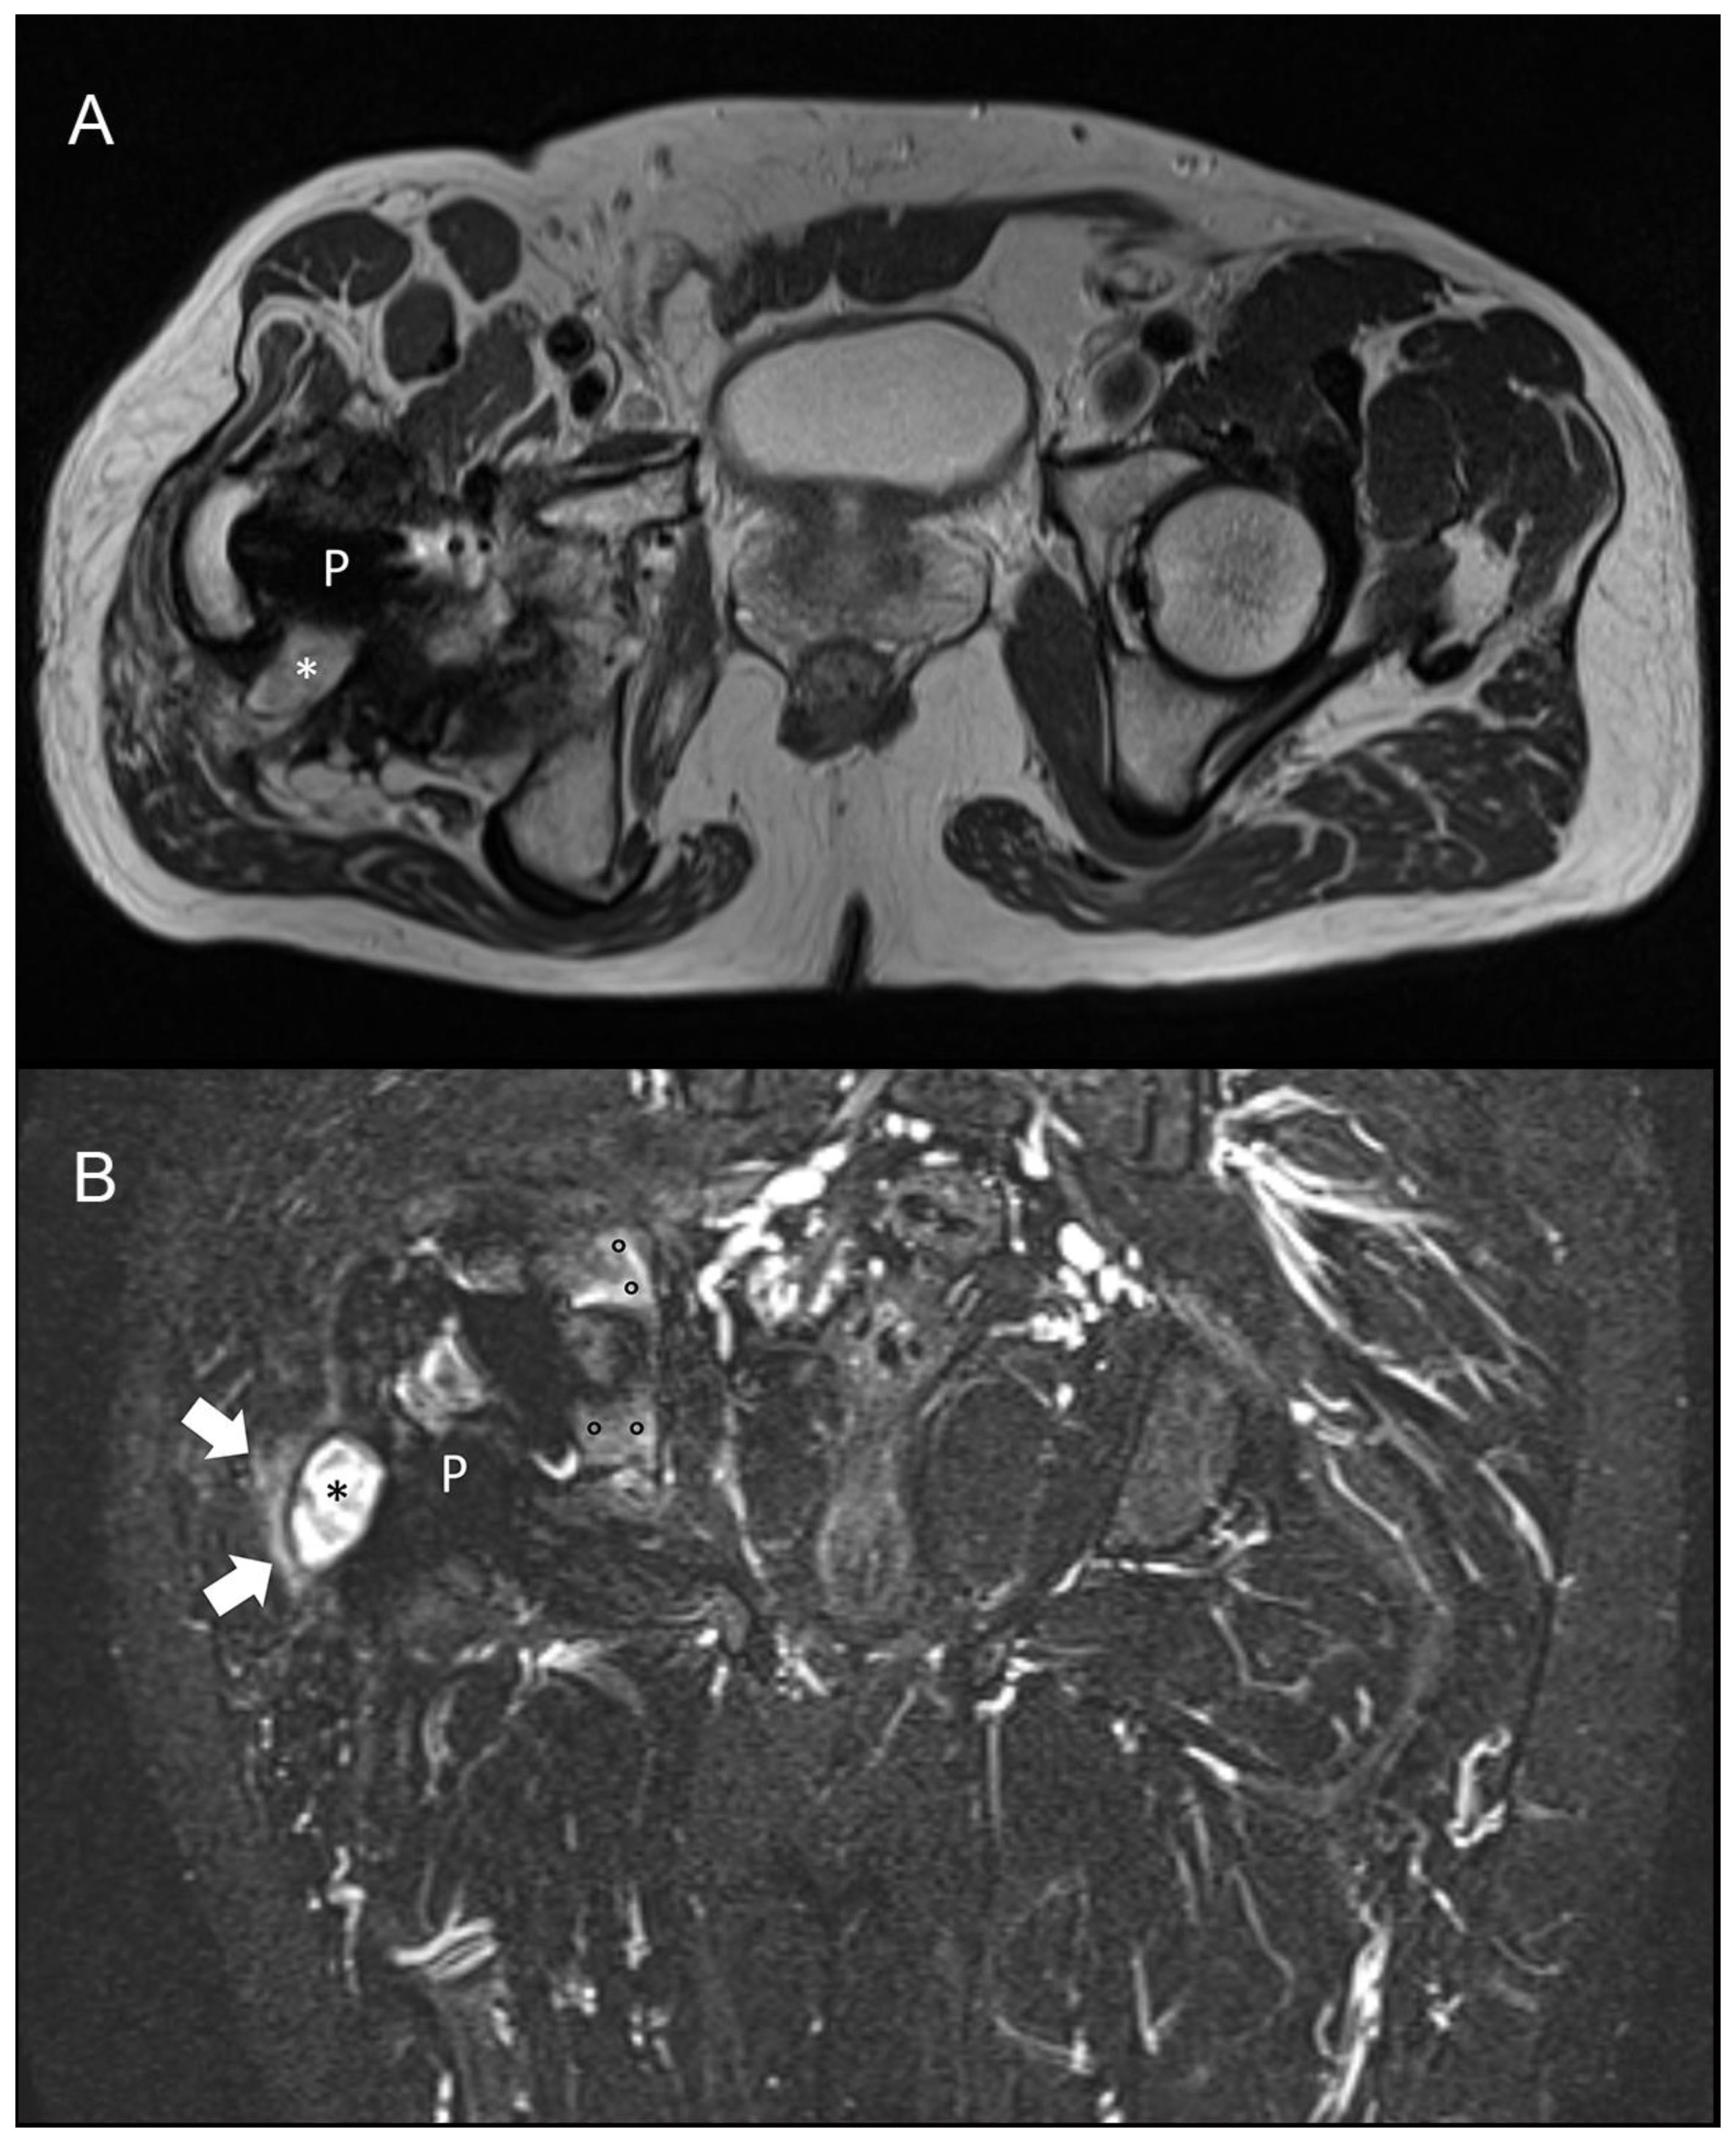

5.4. What Is the Role of MRI to Diagnose a PJI?

- Galley, J.; Sutter, R.; Stern, C.; Filli, L.; Rahm, S.; Pfirrmann, C.W.A. Diagnosis of Periprosthetic Hip Joint Infection Using MRI with Metal Artifact Reduction at 1.5 T. Radiology 2020, 12, 191901. [Google Scholar] [CrossRef] [PubMed]

- Li, A.E.; Sneag, D.; Greditzer, H.G., 4th; Johnson, C.C.; Miller, T.T.; Potter, H.G. Total Knee Arthroplasty: Diagnostic Accuracy of Patterns of Synovitis at MR Imaging. Radiology 2016, 27, 152828. [Google Scholar] [CrossRef]

- Plodkowski, A.J.; Hayter, C.L.; Miller, T.T.; Nguyen, J.T.; Potter, H.G. Lamellated hyperintense synovitis: Potential MR imaging sign of an infected knee arthroplasty. Radiology 2013, 266, 256–260. [Google Scholar] [CrossRef]